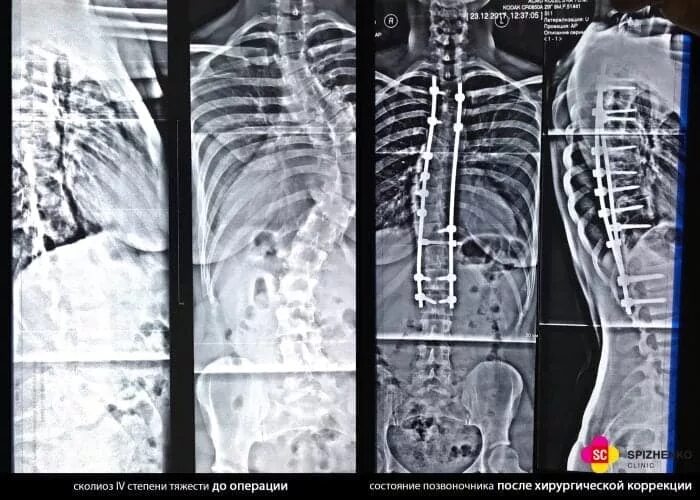

Операция по исправлению сколиоза